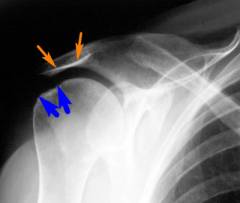

Артроскопия плечевого сустава: ход операции

- Пациента укладывают на операционном столе таким образом, чтобы хирургам было удобно получить доступ к плечевому суставу. Чаще всего его помещают на здоровый бок, а больную руку отводят вверх и осуществляют ее вытяжение при помощи подвешенного груза.

- Осуществляют пункцию плечевого сустава: в него вводят иглу от шприца и подают через нее физиологический раствор. Это нужно для того, чтобы полость сустава растянулась, и в нее можно было ввести артроскоп, не повредив хрящи.

- Затем делают надрез на коже, и суставную полость прокалывают троакаром. Вводят артроскоп и осуществляют осмотр. Через артроскоп в полость сустава подают физиологический раствор для промывания и улучшения видимости.

- При необходимости делают дополнительные проколы и вводят через них хирургические инструменты.